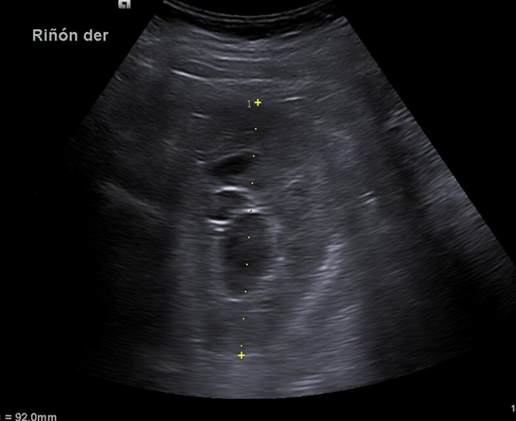

Riñón derecho 9,9 cm con morfología y ecogenicidad conservada. Presenta hidronefrosis grado III. No se identifica causa obstructiva.

Se remite a la paciente a Urgencias donde fue dada de alta con diagnóstico de CRU y tratamiento con Fosfomicina. Consultó al día siguiente, persistiendo el dolor y febrícula, remitiéndose de nuevo a Urgencias. Solicitan estudio de imagen con ecografía y ante los hallazgos se amplió el estudio a TC simple de abdomen: Hidronefrosis grado III con líquido perirrenal sugestivo de rotura de fórnix. Nefrolitiasis puntiformes en ambos cálices inferiores. Sin clara causa obstructiva objetivable. Se contactó con Urología de guardia quien propuso tratamiento ambulatorio con seguimiento posterior y colocación de nefrostomía programas y pielografía para estudio de probable estenosis de unión pieloureteral. Actualmente la paciente permanece en seguimiento por urología.